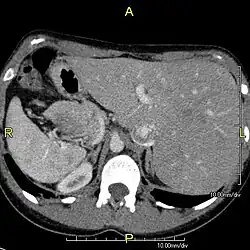

Axial CT image showing situs inversus (liver and IVC on the left, spleen and aorta on the right) in a patient with Kartagener syndrome.